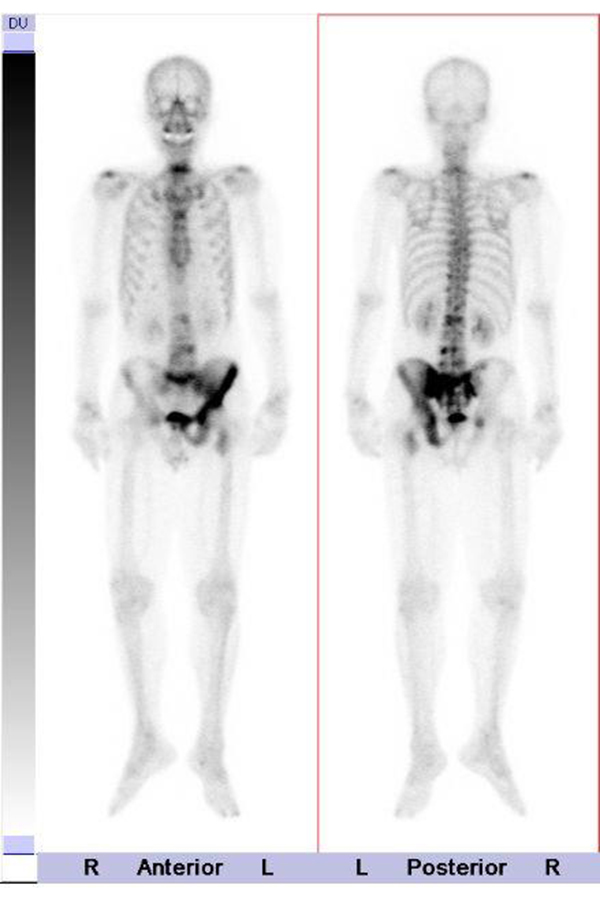

骨シンチグラフィー

腫瘍の骨への転移や骨の炎症、X線では写らない骨折の診断に有用です。

検査は薬を注射し、3~4時間後に撮影を行います。検査時間は30分~1時間程度です。(図5)